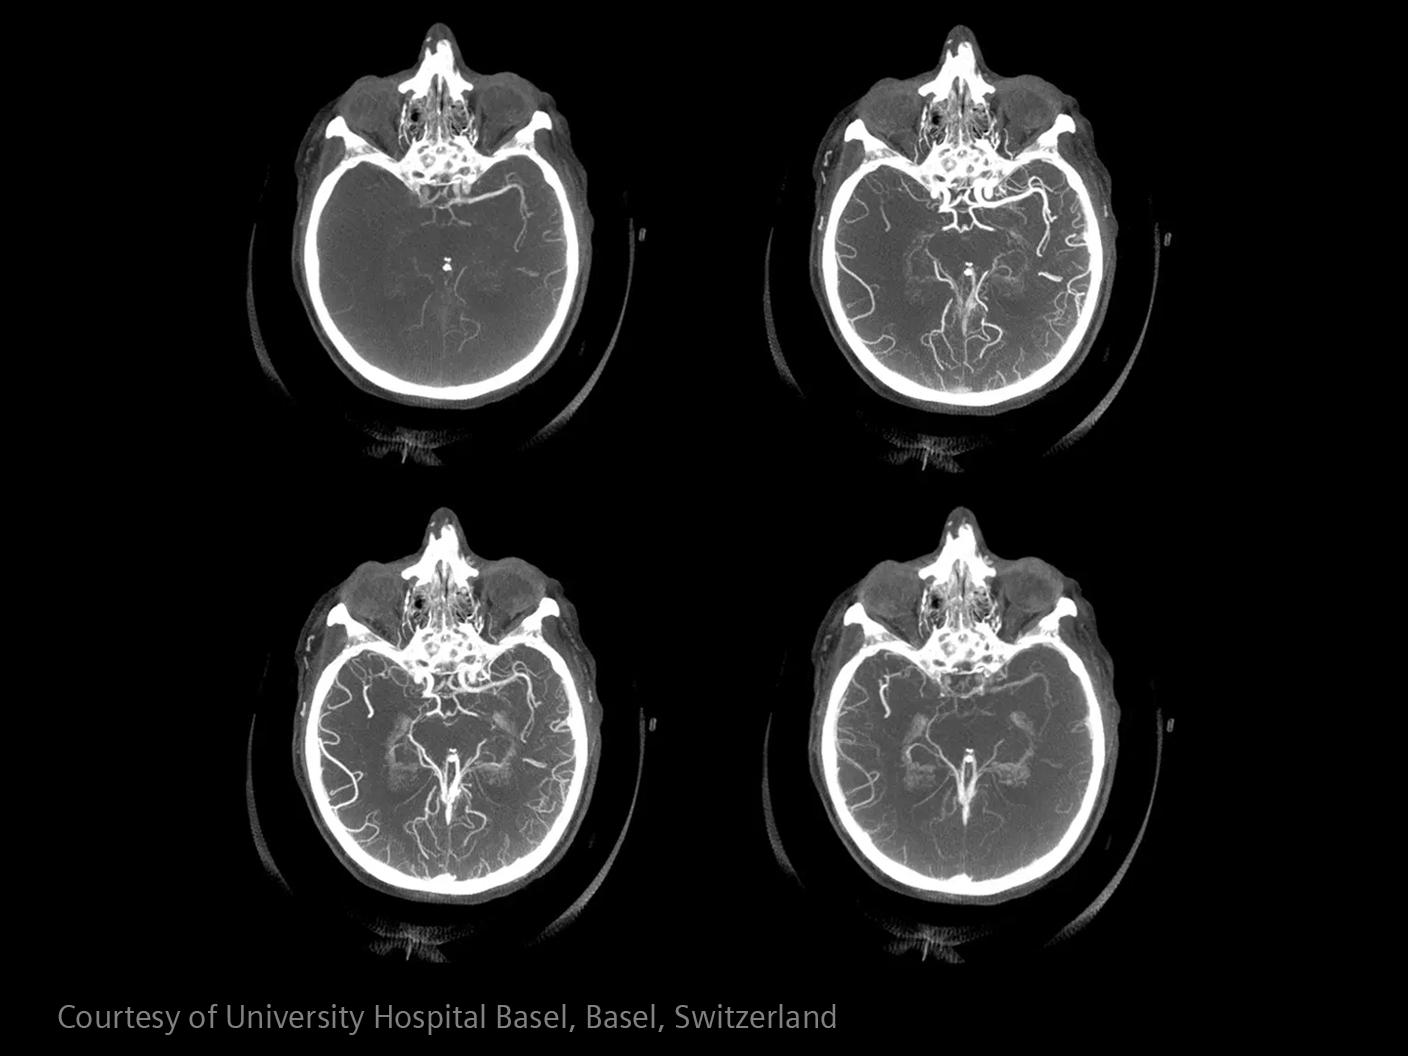

How advanced imaging and AI transform stroke workflow

In stroke care, time is brain. Rapid and accurate imaging is crucial to assess the extent of brain injury and guide immediate treatment. Angiography, MRI, CT, ultrasound, and lab diagnostics are essential tools in identifying stroke type, location, and severity. Advances in imaging technology now allow for even faster acquisition, improved resolution, and enhanced visualization of brain tissue and blood vessels. Innovations such as perfusion imaging, real-time vascular mapping, and AI-assisted diagnostics are transforming stroke workflows and enabling precise, timely interventions.